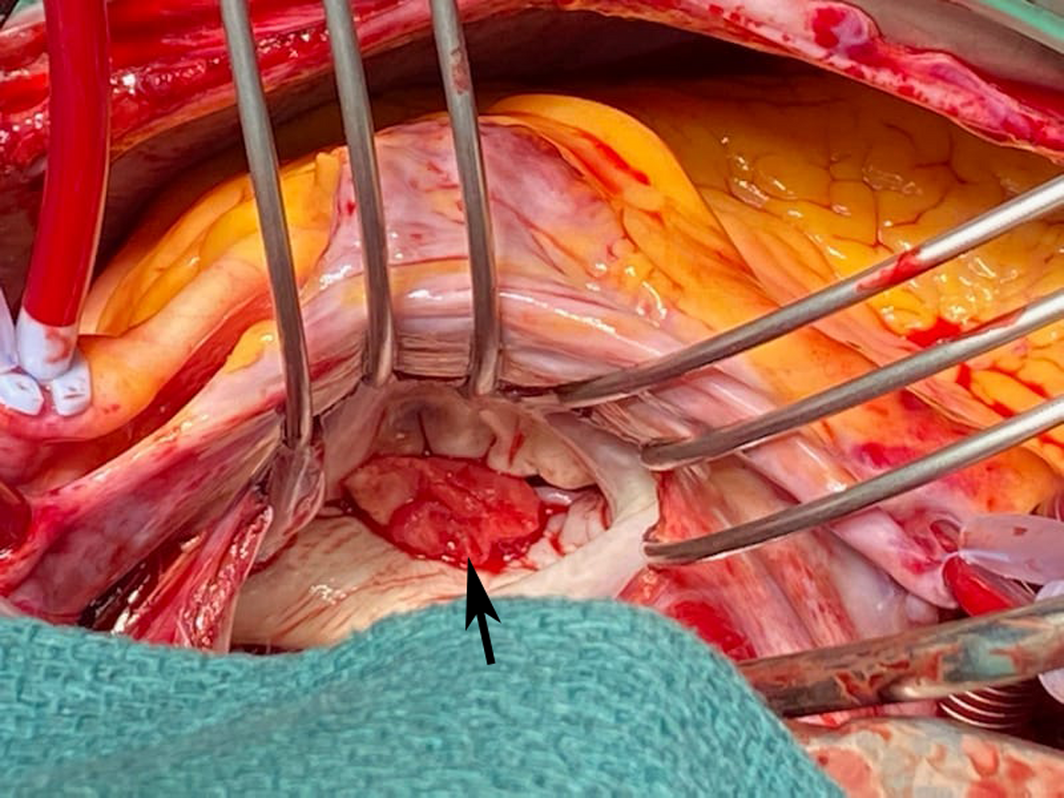

The patient's cardiovascular examination was unremarkable, without stigmata of infective endocarditis or murmur, and a normal electrocardiogram. However, owing to concern regarding infective endocarditis, he proceeded to a transthoracic echocardiogram, which revealed a large, mobile mass fixed to the mitral valve. This was further characterised by transoesophageal echocardiography as a 13 mm × 12 mm vegetation on the anterolateral commissure, associated with progressive mitral regurgitation (Box 1). Left ventricular function was preserved with no other valvular abnormalities. Magnetic resonance imaging suggested a cerebral embolic phenomenon; however, there were no clinical sequelae of stroke. Coronary angiography, as part of surgical workup, revealed no significant coronary artery disease. Despite one week of antimicrobials, following multidisciplinary team discussion, the patient was managed surgically with a vegetectomy (Box 2) and mitral valve repair (bovine patch), curtailing the need for metallic valve replacement, followed by six weeks of IV benzylpenicillin. Despite a stable post‐operative period, the patient presented again with dyspnoea and peripheral oedema. He was found to have recurrence of moderate mitral regurgitation. In consultation with the multidisciplinary team, he was managed medically with diuretics and prolonged infection surveillance. He remains stable with improved inflammatory markers and mild mitral regurgitation on the most recent transthoracic echocardiogram.